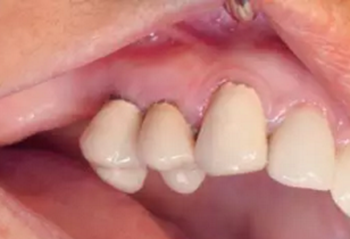

另外,SLA表面可以吸附血漿中的蛋白質(zhì),,并促進(jìn)纖維網(wǎng)狀結(jié)構(gòu)的形成從而加速骨成熟。這對(duì)于拔牙后即刻種植并即刻改善美觀的治療方式來(lái)說(shuō)是一個(gè)巨大的優(yōu)點(diǎn)。術(shù)后10天(圖21)和4周(圖22)復(fù)查,明確牙齦恢復(fù)狀態(tài)和種植體結(jié)合情況。術(shù)后沒(méi)有出現(xiàn)疼痛、水腫或血腫的情況。

圖21

圖22